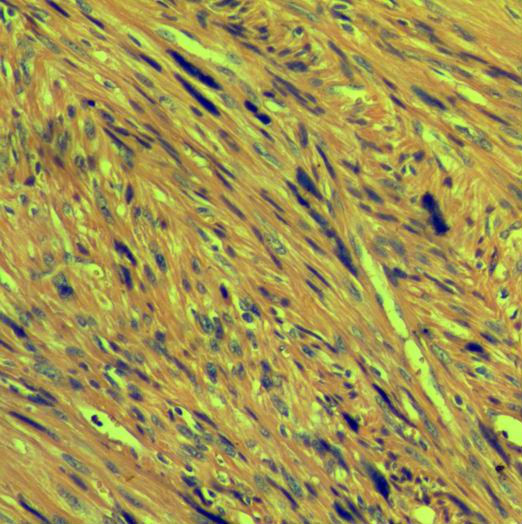

男58岁,发现阴囊肿块两年,与睾丸分界清。送检肿块5*4cm,略呈分叶状,剖面灰黄均匀实质,镜下见梭形细胞密集,大量异形细胞,可见核分裂,约5个/10HPF。想问一下,这种表浅平滑肌肿瘤怎么报啊。

谢谢王老师,我仔细找过了,核分裂数超过5个/10HPF,拟诊断平滑肌肉瘤。